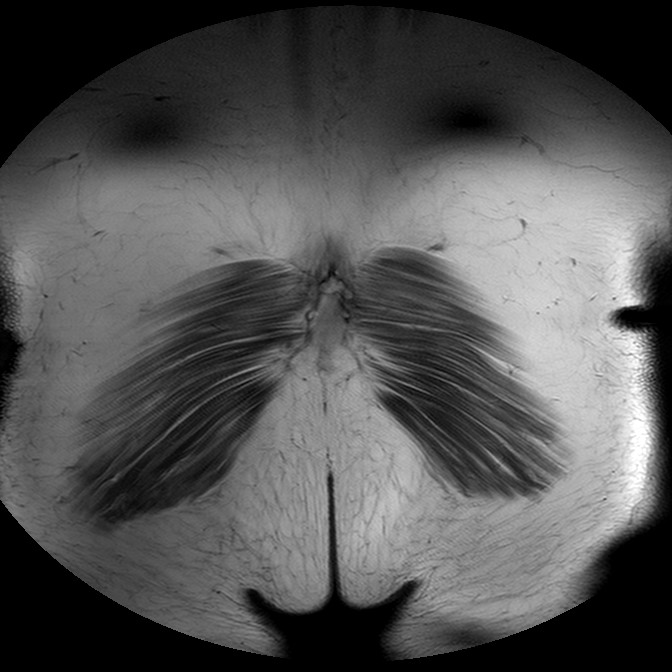

Esami: RMN BACINO

T1w TSE

Evidenti e simmetriche alterazioni osteofitosiche in regione coxo femorale con riduzione delle rime articolari. Degenerazione completa del cercine glenoideo. Non attuali segni di versamento articolare. Non segni di edema osseo che escludono attuale algodistrofia od osteonecrosi. Lieve e simmetrica riduzione del trofismo della muscolatura glutea.